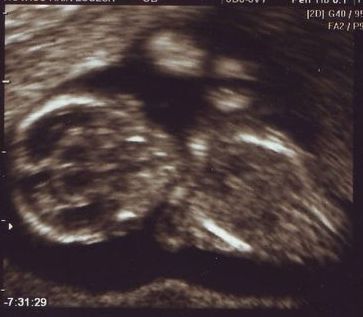

Mi tegnap voltunk dokinál, már 17 mm a picikénk, és élénken ver a kis szíve. :D Haematómából már csak egy alig látható vákony csík van, el fog az is tűnni. :D

olyan szépen látszik a picur,kis édes :)

hatalmas bébikéd van :D az a lényeg h elmúllik a hematoma.

Csillag: Most 5.5 cm a fejétől a popóig. :) A vonalzón ugyan nem ennyit ír, de az egy hétre vonatkozik. Minden rendben van vele egyébként. Megyek majd integrált tesztre...